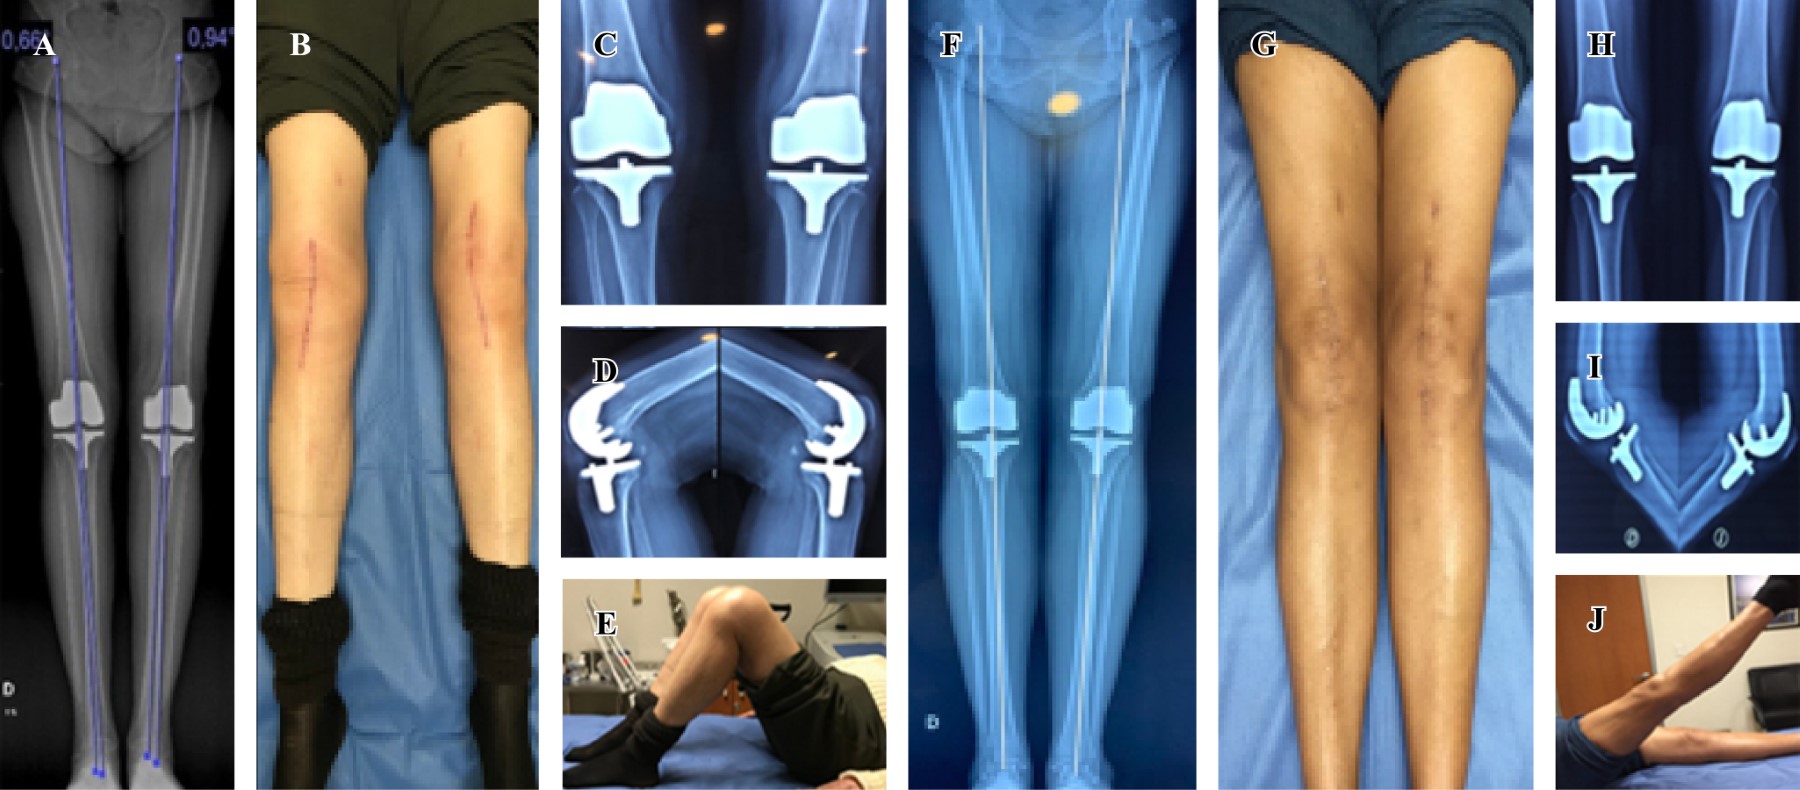

En relación al eje mecánico, 100% de los pacientes intervenidos tienen una desviación entre 0o y 2o en el plano coronal (Figura 1). La función con los resultados de la escala de WOMAC prequirúrgica y postquirúrgica mostró una media de 22.71 ± 3.34 prequirúrgica y 4.16 ± 1.84 postquirúrgica, con diferencias estadísticamente significativas p = 0.000 (IC 95% de 17.16 a 19.92) (Tabla 1).

En relación a la movilidad articular de flexoextensión bilateral obtenemos mejoría con diferencias clínicas significativas tanto derecha como izquierda con p < 0.05 (Tabla 1). Se muestra resultado clínico y eje mecánico radiográfico de cuatro pacientes a diferentes años postquirúrgicos (Figuras 2 y 3).